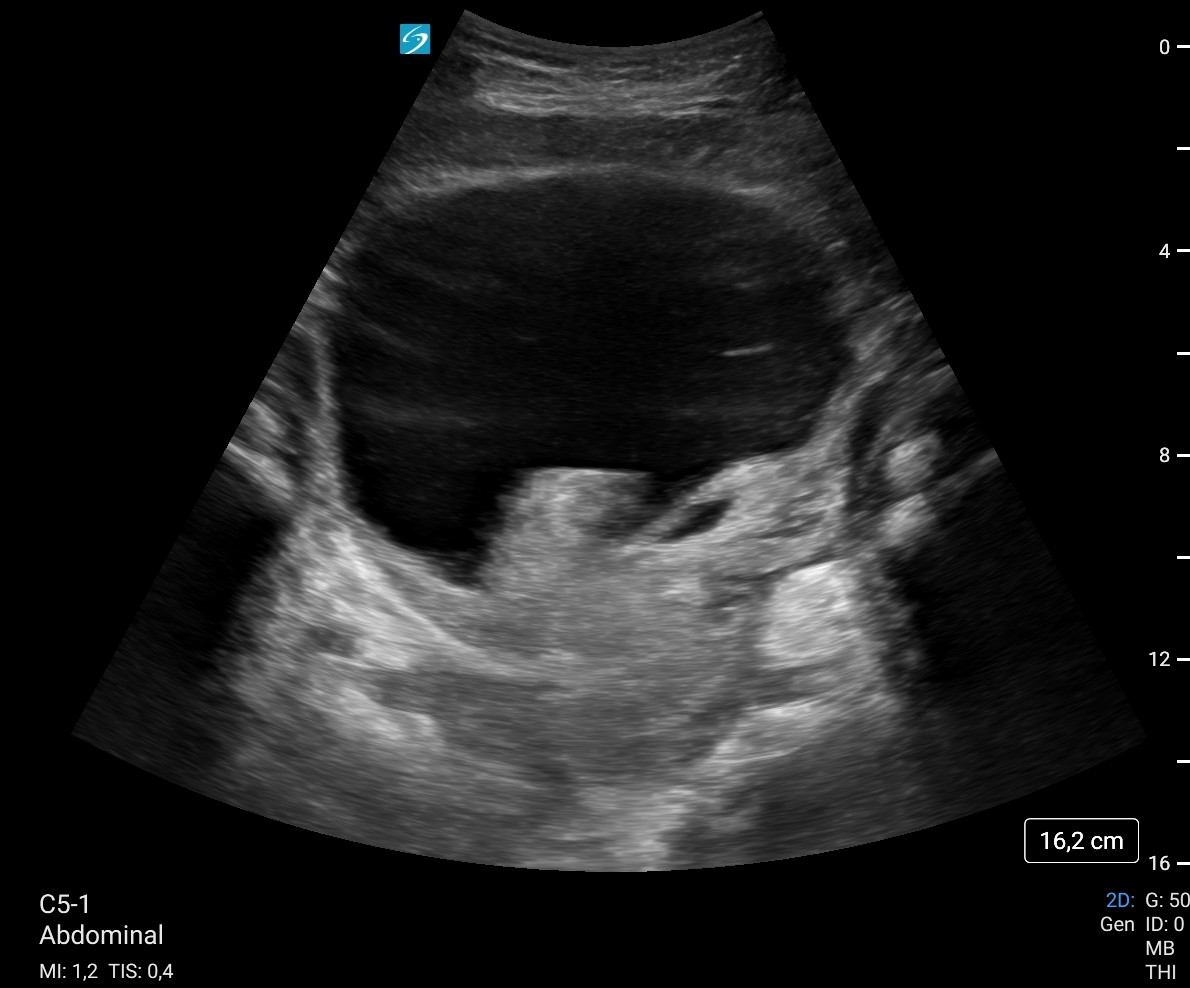

Ecografía a pie de cama: Vejiga 700 cc con imagen hiperecogénico intravesical, irregular, pensando en coágulo como primera opción sin poder descartar tm vesical. Sospecha de retención aguda de orina (RAO) con probables de coágulos intravesicales vs posible tumor vesical.

Vejiga urinaria a máxima repleción, identificando contenido hiperecoico de morfología tubular en pared lateral inferior izquierda, parece desplazarse a los meatos con los cambios posicionales, lo que sugiere existencia de coágulos como primera posibilidad, sin poder descartar tumor subyacente. Se recomienda valoración con cistoscopia, lavados vesicales...